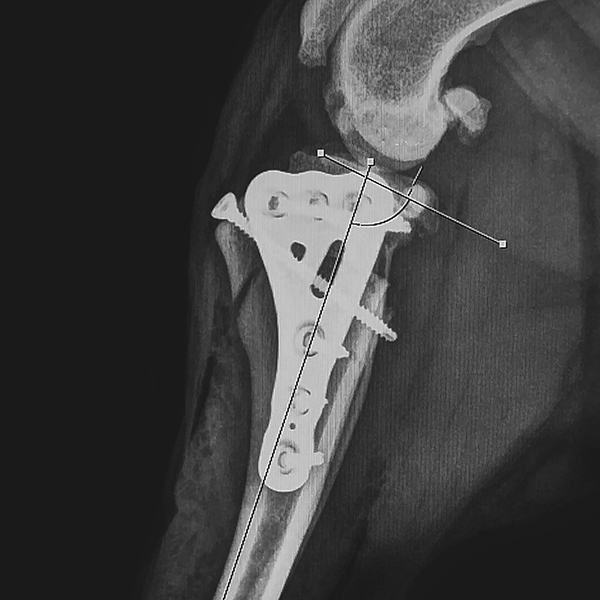

Die CORA-basierte Leveling-Osteotomie (CBLO) ist ein relativ neuer Ansatz und eine Technik zur Behandlung des Kreuzbandrisses, insbesondere bei Hunden. CBLO - Implantate nutzen eine korrektive Osteotomie-Technik, die der TPLO ähnelt, indem sie die Position des Tibiaplateaus modifiziert, um die Gelenkstabilität wiederherzustellen. Beide Verfahren beinhalten eine radiale Osteotomie, um das Tibiaplateau zu begradigen.

Bei der TPLO wird jedoch ein halbkreisförmiger Schnitt in der proximalen Tibia vorgenommen, und das distale Fragment wird rotiert, um ein ebenes Tibiaplateau zu erreichen. Im Gegensatz dazu konzentriert sich die CBLO darauf, den Winkel des Tibiaplateaus zu verändern, indem das Sägeblatt am „Center of Rotation of Angulation“ (CORA) angesetzt wird – also in einer invertierten Position relativ zum Tibiakopf. Dies ermöglicht eine kraniale Rotation.

Diese einzigartige Vorgehensweise optimiert nicht nur die Hebelwirkung des Tibiaplateaus, sondern erleichtert auch die Vorverlagerung der Tuberositas tibiae. Durch den Einsatz dieser innovativen Technik zielt die CBLO darauf ab, verschiedene Herausforderungen im Zusammenhang mit Kreuzbandverletzungen zu bewältigen. Dazu gehören unter anderem sekundäre (spät auftretende) Meniskusverletzungen, die Überlastung des Kaudalen Kreuzbandes, die Reduktion der Achs- und Sekundärverschiebungen, sowie die Fehlstellung der Gelenksflächen.